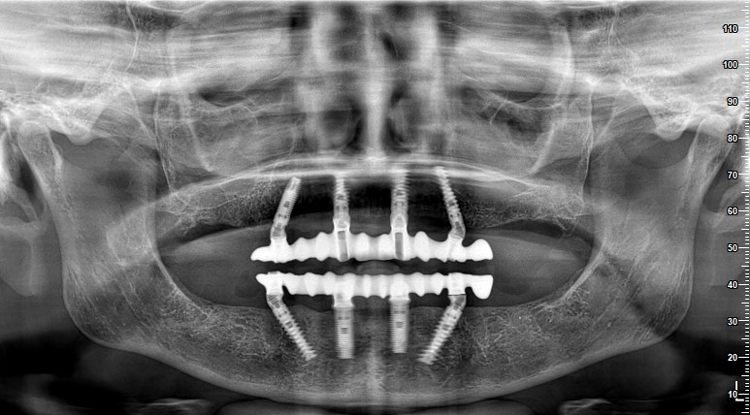

![]() |

| Hình Xquang sau khi đặt All-on 4 implants cho bệnh nhân J.C |